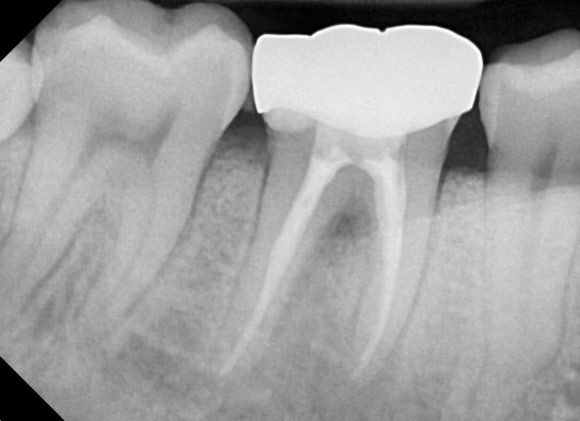

20250127

현상태를 확인해봅니다.

뿌리 끝에 어두운 염증주머니가 보입니다.

(좌) 재신경치료 전 (우) 재신경치료 후 (20240329)

뿌리 끝에 매달려 있던

검은 그림자의 내부로

몽글몽글 새 뼈가 재생되는 것을

관찰할 수 있습니다.